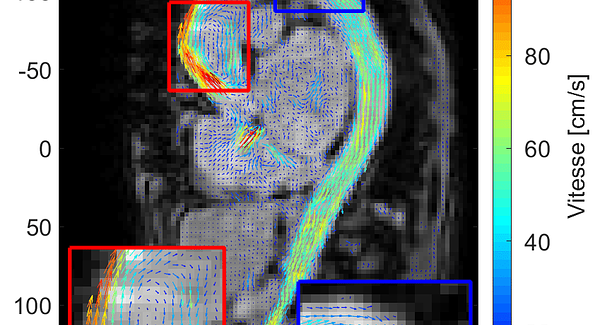

Cyceron est une plate-forme d'imagerie de 8000 m² au sein de laquelle sont menées depuis 1985 des recherches biomédicales principalement dans le domaine des neurosciences, des cardiosciences et de la cancérologie. Il réunit également un ensemble unique de laboratoires et d'équipements, hébergeant 250 chercheurs, enseignants-chercheurs, ingénieurs, techniciens et étudiants répartis au sein d'une unité de service et de 7 unités de recherche, véritables vecteurs des activités scientifiques de Cyceron.